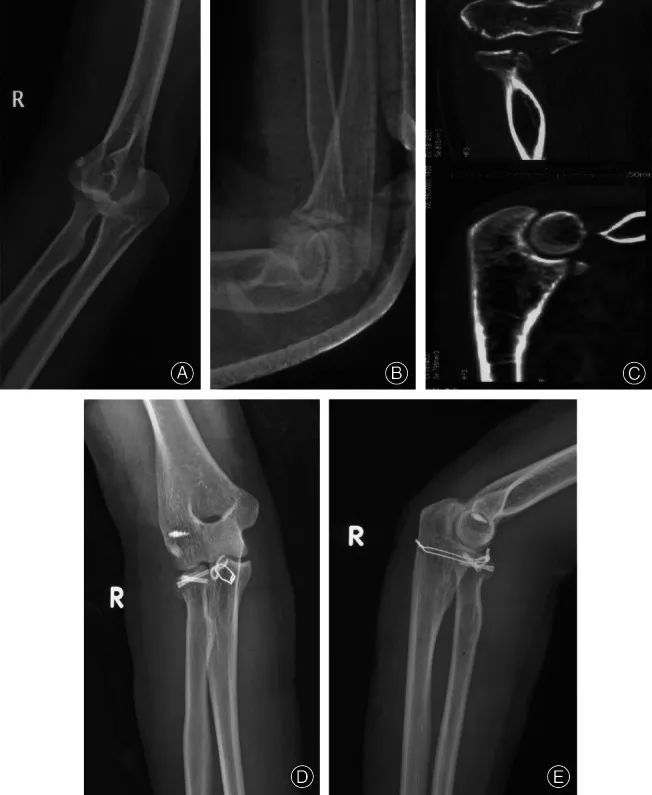

图11 右肘恐怖三联征,尺骨冠状突用环形钢板固定,桡骨头用埋头带槽钉固定,外侧韧带复合体用螺纹铆钉修复。肘关节术前X线检查(A、B)CT检查(C)。术后第二天肘关节X线检查(D,E)。